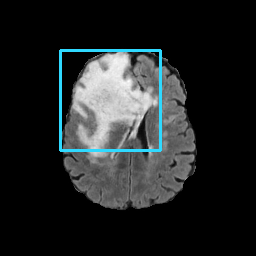

Figure 7: Lossy image reconstructions on CT (row 1, 2) and MRI (row 3, 4) images, where the row 2, 4 provide a zoomed-in view of the bounding box region of the row 1, 3. The leftmost column represents the target images, while the subsequent four columns show the stolen images reconstructed by the decoder D or D1 in two scenarios.

A visual comparison between target and stolen images is available in Fig. 7. We observe that the stolen images from IT Scenario closely resemble the input ones, particularly in the tumor regions, whereas stolen images from EP Scenario exhibit blurring artifacts in finer details. In both cases, the stolen images reconstructed by D1D1 demonstrate a comparable quality to those reconstructed by DD, thus further confirming the effectiveness of the reduced decoder D1D1.